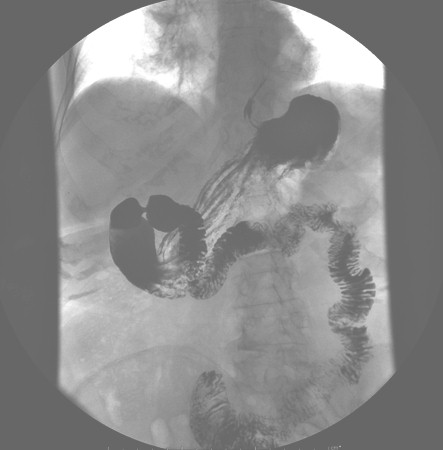

In the postoperative period did gastroduodenal transit (Photo 5) confirming the good passage of contrast and the indemnity of the digestive wall.

In reviewing in the consultation was again requested an endoscopy and gastroduodenal transit (Photo 6) turning to check the normal evacuation and the adequate location of the esophagogastric junction.